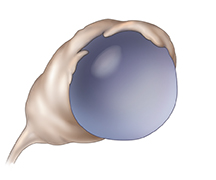

Functional cyst

A functional cyst is the most common kind of cyst. It forms when a follicle doesn't release a mature egg or continues to grow after releasing the egg. Functional cysts often occur on only one ovary at a time. They often shrink on their own in 1 to 3 months. In rare cases, a cyst will break open (rupture), causing pain. Pain might also be caused by the twisting of an ovary that is enlarged because of the cyst growing on it.